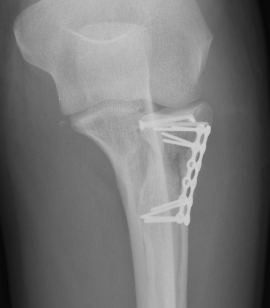

ORIF with plates

Technique

Lateral approach

- identify safe zone (90 degrees between radial styloid) and Lister's tubercle)

- lag articular surface first if required

- pre-contoured low profile plates

- distal limit is bicipital tuberosity

- check ROM intra-operatively

- plates often bulky and may limit ROM

- close annular ligament